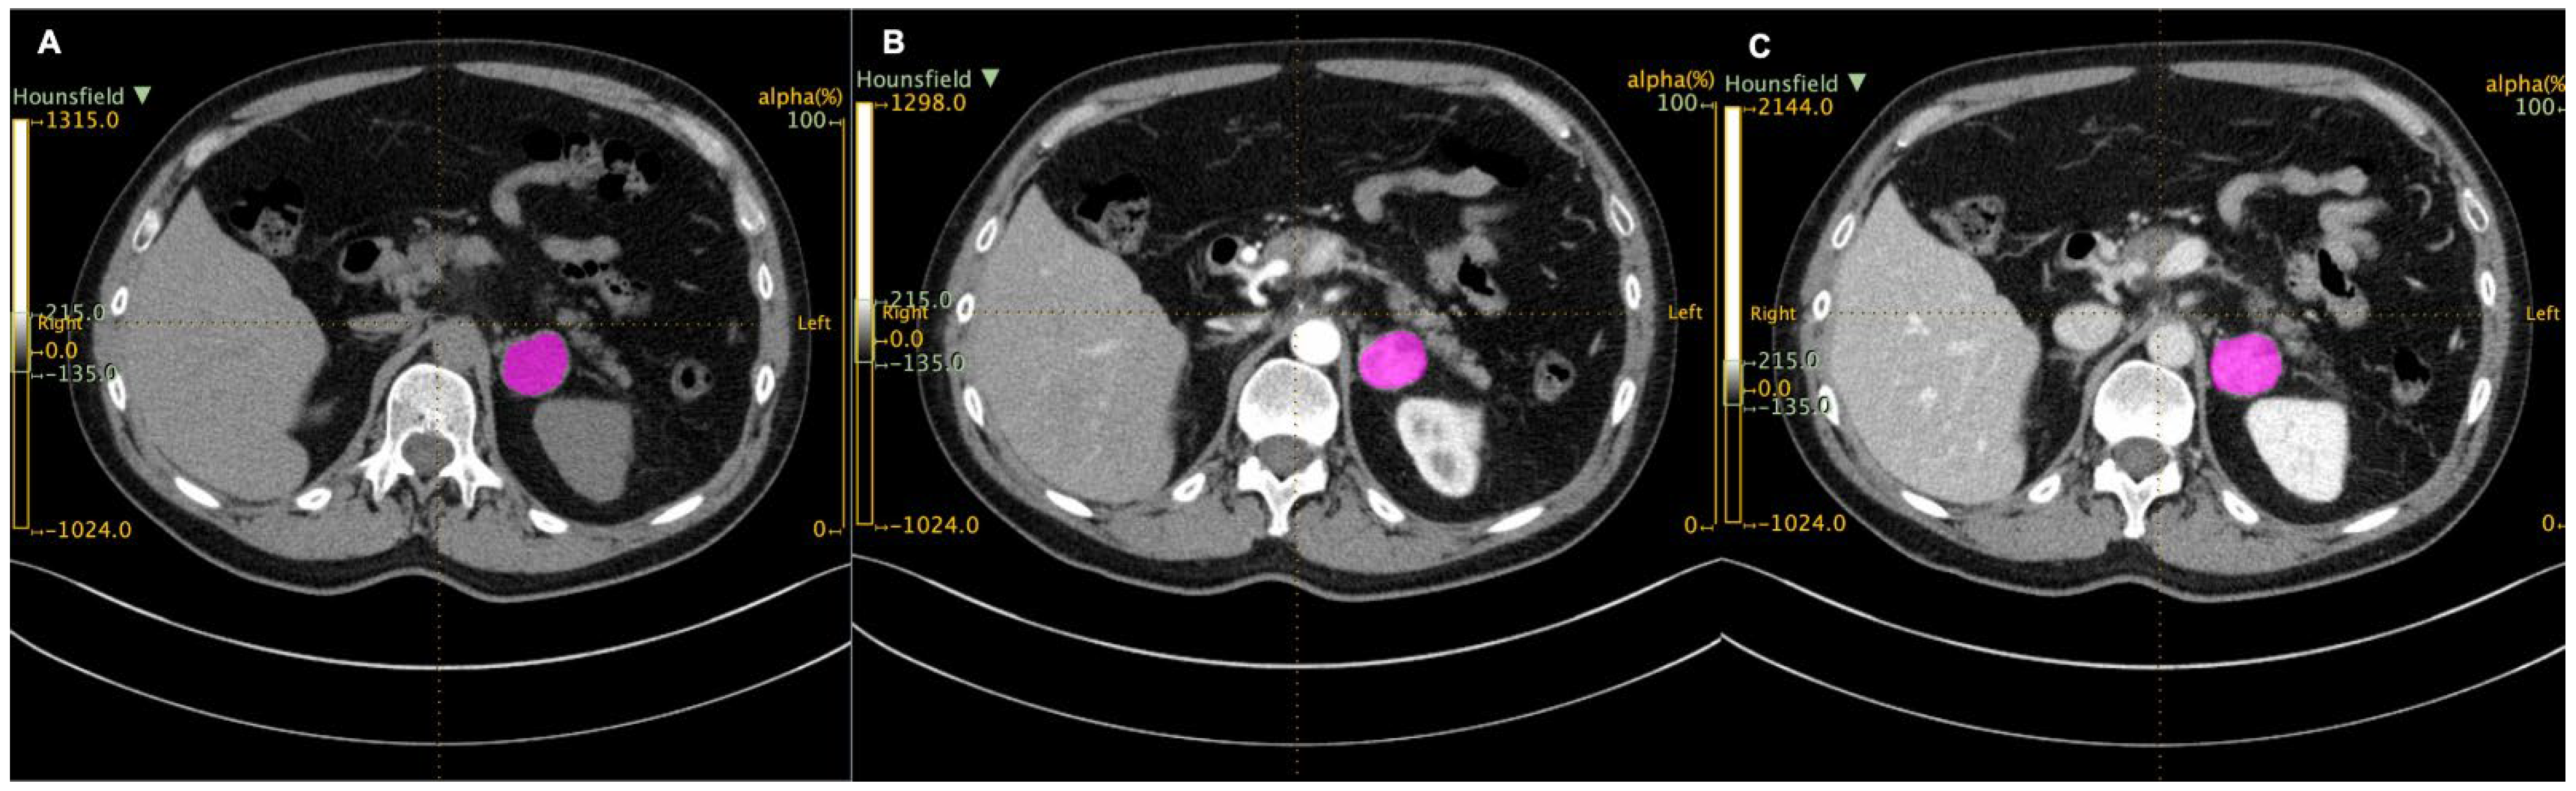

2.2. Image Analysis